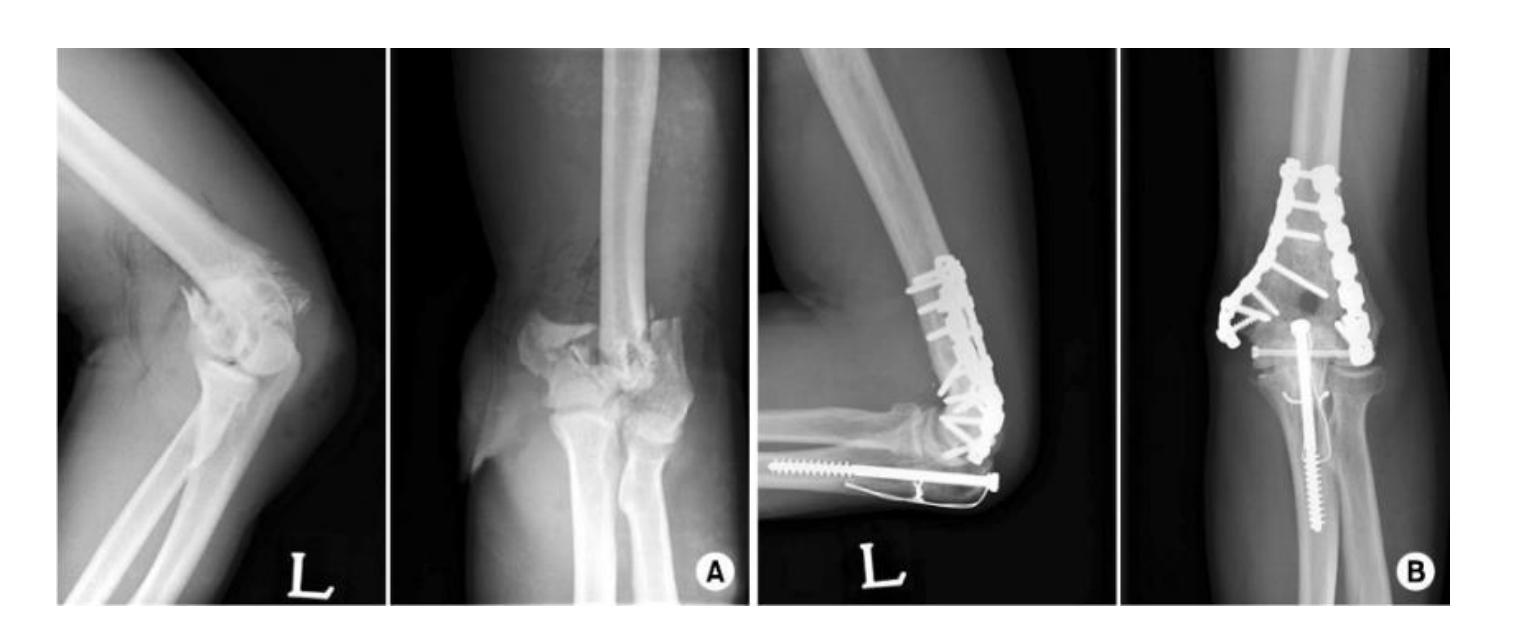

A 35-year-old male with this fracture, how would you treat it?

- Open reduction and internal fixation

Q15: 35-year-old male with fracture - Treatment

35 years old male with this fracture, how would you treat it:

- Open reduction and internal fixation of ulna - Closed reduction of head of radius +/- fixation